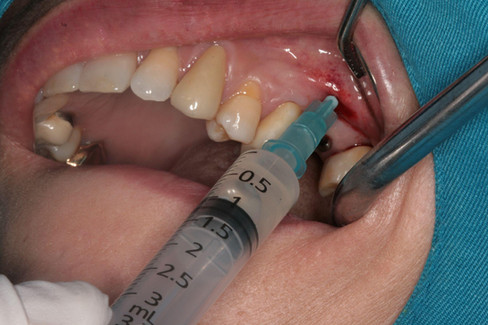

Following local anesthesia with one carpule of lidocaine, a minimally invasive incision was made, and a lateral window approach to the maxillary sinus was performed using a round bur.

Through the lateral window, purulent sinus exudate was aspirated using a 10cc syringe, resulting in a syringe filled with discharge.

After aspiration, the maxillary sinus was irrigated with sterile saline, followed by direct injection of a solution containing 1g of Ceftizoxime sodium (Ceftezole sodium) mixed with 1cc of sterile distilled water into the sinus cavity.

Additionally, Augmentin was prescribed orally for 10 days to provide systemic antibiotic coverage.